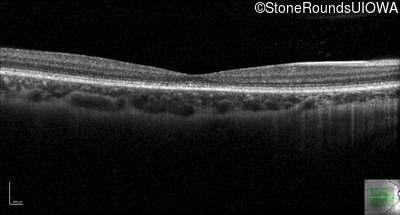

Cone and Cone Rod Dystrophy (IA1b)

Age at visit: 16 years

This 16-year-old female complains of difficulty tracking softballs in flight. Her parents first noticed problems with her vision at age 3 when she would turn slightly away from objects to look at them. There is no family history of vision loss.

Cone and Cone Rod Dystrophy GUCY2D Arg838Cys CGC>TGC   AD